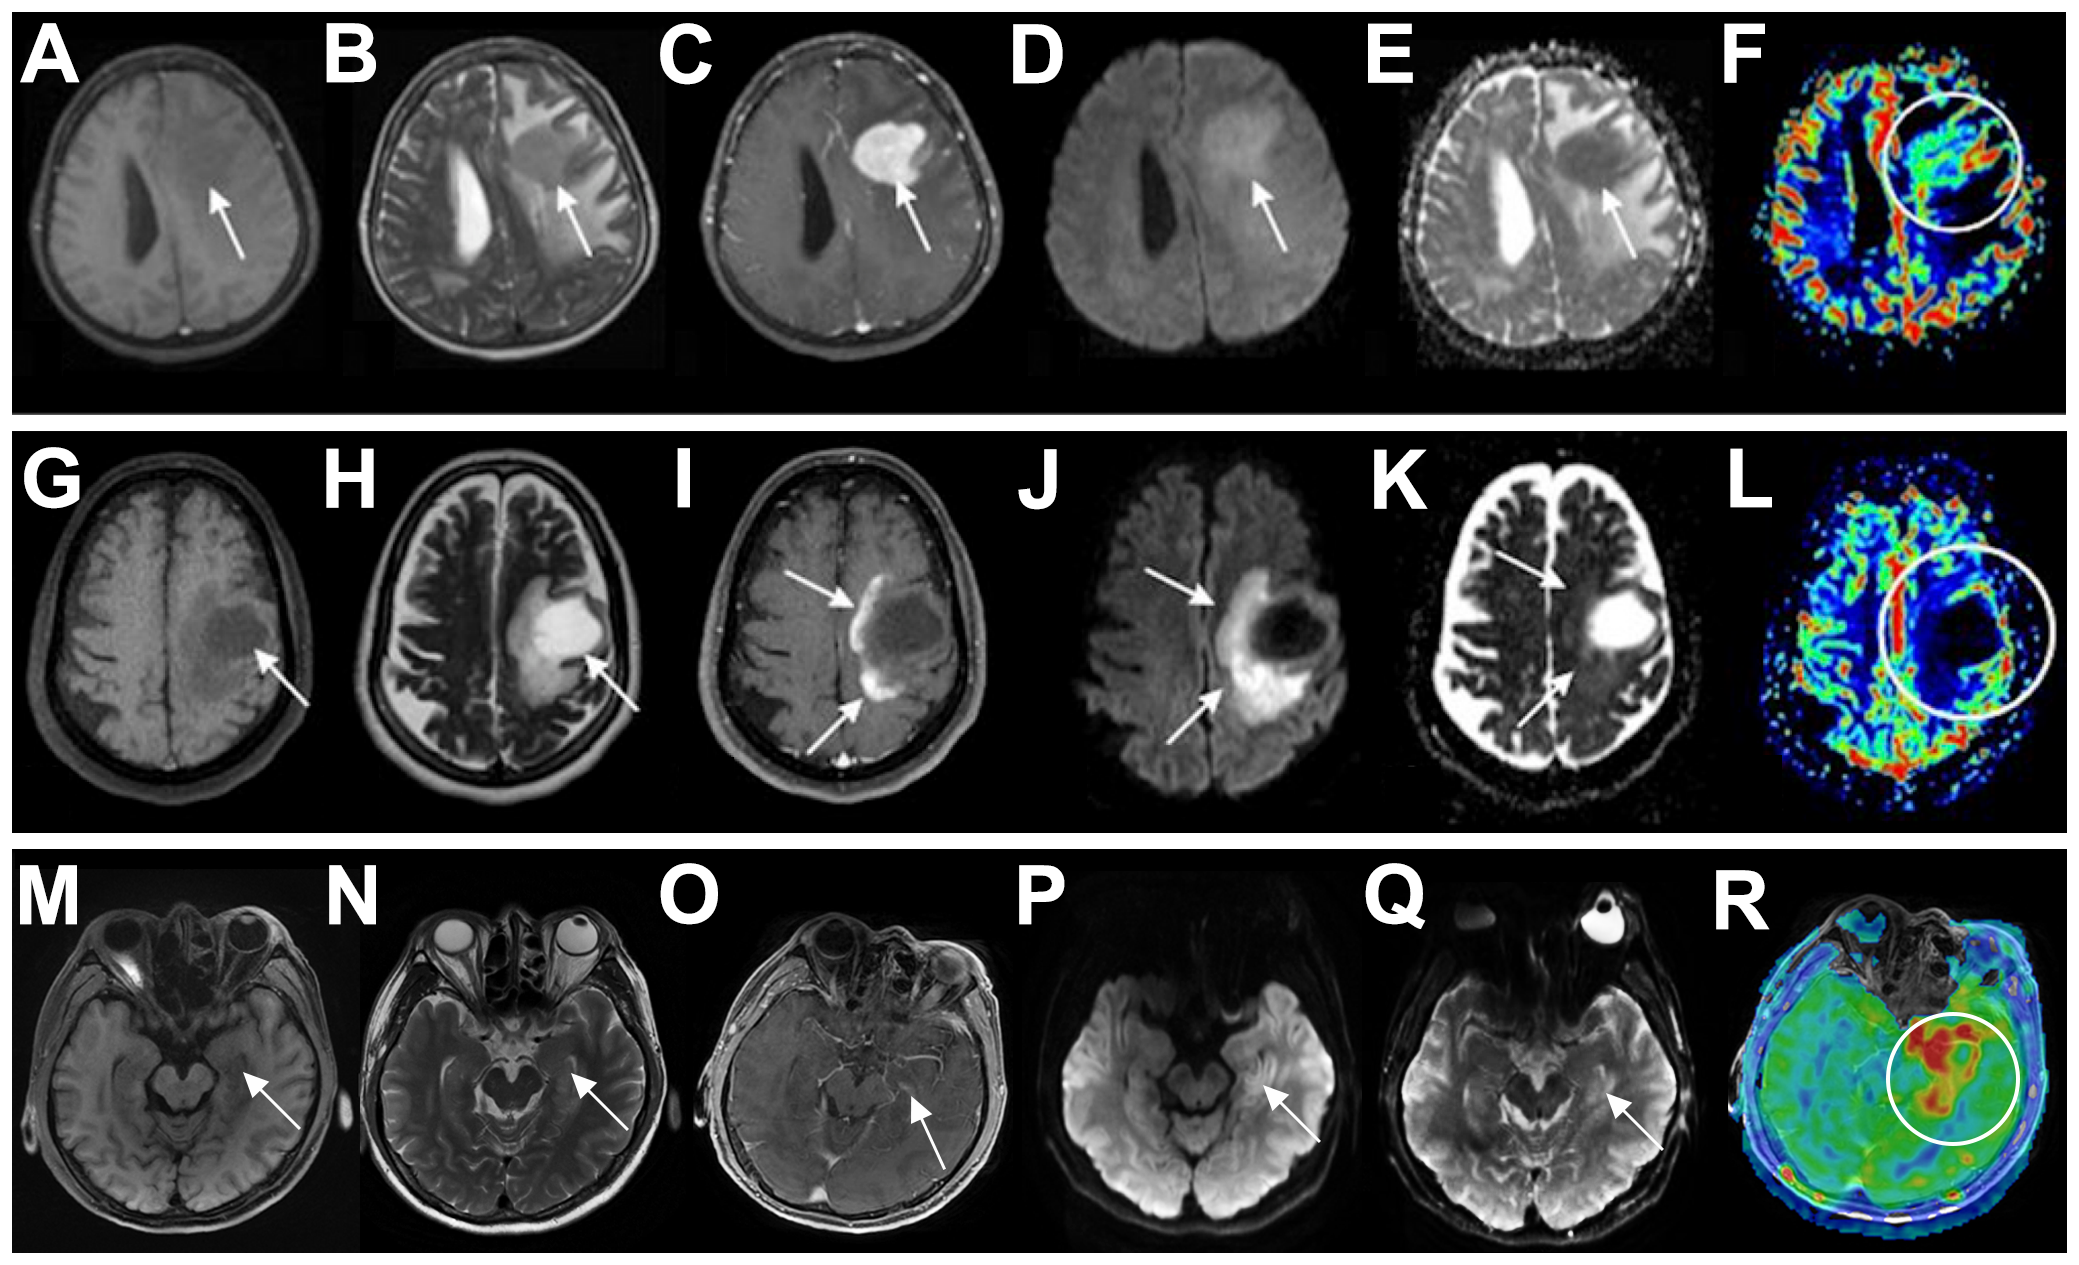

Lymphoma is a great mimicker with a challenging differential diagnosis. PCNSL is very challenging to differentiate from demyelinating diseases, especially in young immunocompetent patients. Demyelinating diseases often have an acute or subacute onset, with a relapsing course, and often have a history of infection or vaccination before onset, but the clinical presentation is nonspecific. Immune markers can be positive in CSF. On imaging, tumefactive demyelinating lesions (TDLs) is the most difficult to distinguish from PCNSL. The features of TDLs include ring enhancement, iso- and high-mixed signals on T2, and the absence of cortical involvement and mass effect (4). PCNSL showed strong diffusion restriction, whereas TDLs showed increased apparent diffusion coefficient (ADC). Although acute demyelinating lesions may have peripheral diffusion restriction corresponding to ring enhancement areas, the ADC of TDLs is not as low as that of PCNSL (5). The specific clinical and radiographic differences between PCNSL and TDLs are detailed in Table 3 (6, 7) and illustrated in Figures 3A–L (8).

Figure 3

Differential diagnosis of PCNSL in immunocompetent patients. (A-F) A 71-year-old woman with PCNSL. The patient presented with a solid expansive lesion in the left frontal white matter, characterized by low signal on T1 (A) and T2 (B), with homogeneous contrast enhancement (C). The lesion exhibited high signal on DWI (D) and low signal on the ADC map (E). rCBV imaging showed mild hyperperfusion [circle in (F)]. (G–L) A 41-year-old woman with TDLs. The patient presented with an expansive lesion in the left subcortical frontal white matter, showing low signal on T1 (G) and high signal on T2 (H), accompanied by perilesional edema and incomplete ring-enhancement (I). The lesion also demonstrated incomplete peripheral restricted diffusion on DWI (J) and ADC maps (K) and no signs of hyperperfusion on rCBV imaging [circle in (L)]. (M–R) A 58-year-old man with herpes simplex encephalitis. The left medial temporal lobe was swollen, exhibiting slightly low signal on T1 (M) and high signal on T2 (N), with no significant contrast enhancement (O). The lesion presented slightly restricted diffusion on DWI (P) and ADC maps (Q) and hyperperfusion on rCBF imaging [circle in (R)]. Arrows indicate lesions. PCNSL, primary central nervous system lymphoma; DWI, diffusion-weighted imaging; ADC, apparent diffusion coefficient; rCBV, relative cerebral blood volume; TDLs, tumefactive demyelinating lesions; rCBF, relative cerebral blood flow.

The differentiation between PCNSL and viral encephalitis (mainly herpes simplex encephalitis) is relatively simple. The latter has an acute onset, often with fever and prodromal symptoms. A key differential feature on MRI is the presence of hemorrhage in herpes simplex encephalitis, which causes mixed signal changes on T1- and T2-weighted images, whereas PCNSL is usually nonhemorrhagic. Moreover, the serum virus antibody titer of herpes simplex encephalitis is markedly elevated, the CSF virus PCR test is positive, the disease course is self-limited, and antiviral therapy is effective. As the disease progresses, viral encephalitis can be quickly excluded in patients with PCNSL. Pierre Giglio et al. reported a case of PCNSL mimicking the clinical and MRI features of herpes simplex encephalitis. The patient was diagnosed by biopsy after antiviral treatment failed to improve the symptoms and images (9). The specific clinical and radiographic differences between PCNSL and herpes simplex encephalitis are detailed in Table 3 (10–12) and illustrated in Figures 3A−F, M−R).